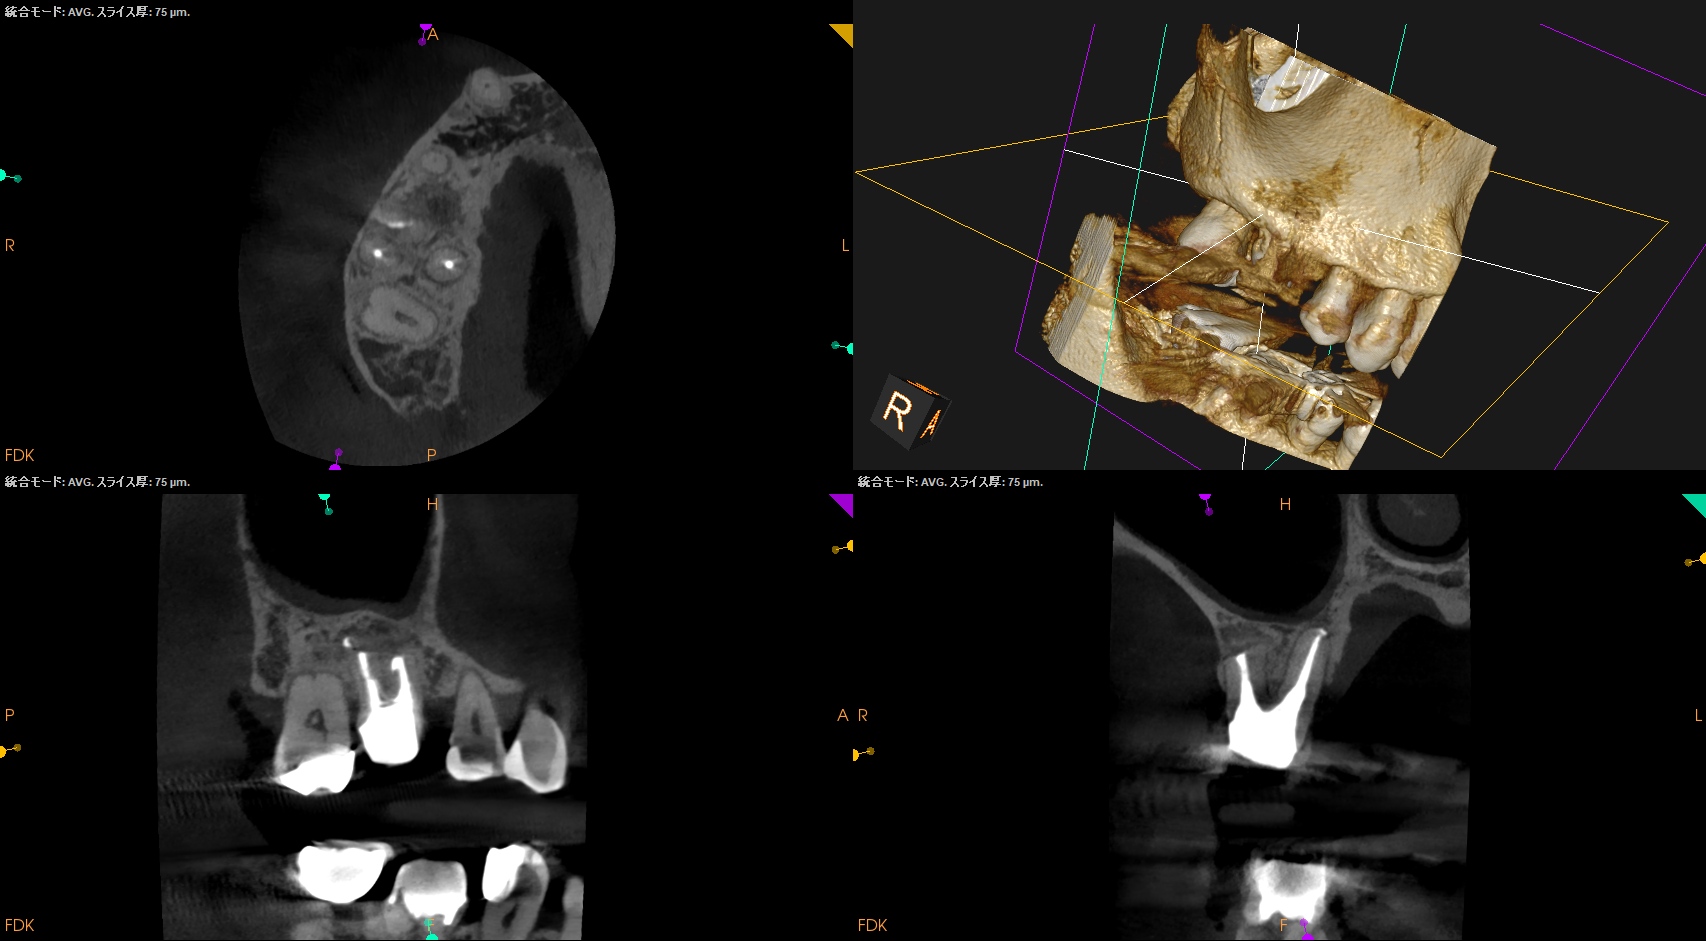

Pre-op Endo test(2025.8.25)

MB

DB

P

MB,DB,P全ての根管に根尖病変がある。

PのP側皮質骨はかなり減少している。

これが歯周病が原因か?と言えば、

術前の検査で歯周ポケットが正常値(Within Normal Limit)なため、恐らくエンドが原因でこのようになっているのだろう、と推測できる。